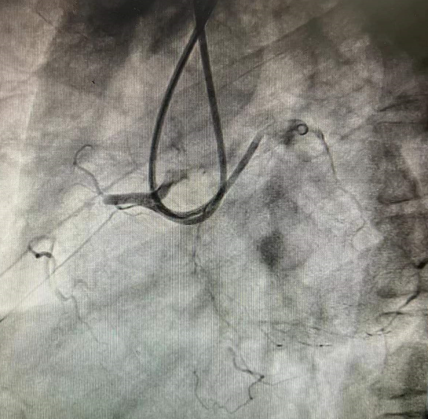

CAG分析及策略制定:冠状动脉造影提示右冠近段闭塞:

患者右冠近段齐头闭塞、闭塞段长、伴钙化,侧枝循环血管条件差,考虑逆向成功率较低。

PCI过程:术中首先尝试正向开通(AWE),逐步升级导丝,均多次进入内膜下,反复尝试不能送入远端真腔,王健主任果断启动正向ADR技术,利用Corsair微导管于右冠近段制造正向夹层,使用专用器械Stingray球囊,Gaia Third导丝穿刺,

成功通过血管内膜下重新进入远端血管真腔,经过多体位投照、逆向造影均证实为真腔,顺利开通闭塞病变。

正向造影可见右冠全程弥漫狭窄病变